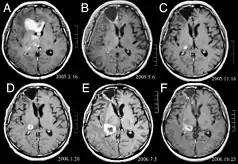

![]() Glioblastoma arising in an astrocytoma. This spinal cord exhibits both a lightly staining microcystic astrocytoma as well as a darkly staining glioblastoma. | |